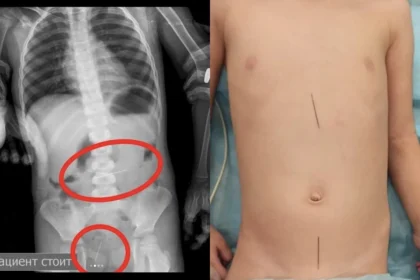

Дәрігерлер ине жұтып қойған үш жасар баланы аман алып қалды

Бала төрт ине мен жүгірткі (бегунок) жұтып қойған. Бүлдіршіннің анасы ұлының ине…